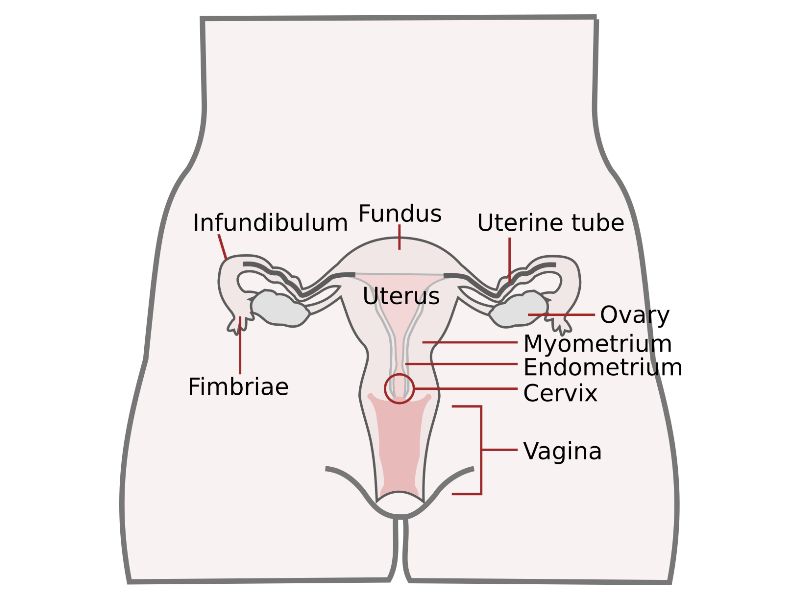

Uterus

Slide 88

Uterus

3 regions3 layers

Three regions

FundusBody

Cervix

Three layers

- Endometrium

- Formation placenta

- Myometrium

- Enlarge during pregnancy

- Expulsion fetus & placenta

- Adventitia

Vagina

Slide 90

Vagina